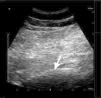

El síndrome piriforme es una causa poco frecuente de dolor de espalda y miembros inferiores. Algunas de las opciones de tratamiento incluyen la inyección del músculo piriforme con anestésicos locales y corticoides. Se han descrito varias técnicas de inyección. Las técnicas ecoguiadas permiten la visualización directa del músculo y la inyección en tiempo real. Se presenta una serie de 5 pacientes cuya clínica es compatible con síndrome piriforme, que no han mejorado tras tratamiento farmacológico. Se optó por la inyección del músculo piriforme con anestésicos locales y corticoides mediante un nuevo abordaje ecoguiado más sencillo técnicamente, basado en la técnica estándar. En los 5 pacientes se apreció una mejoría del dolor medido por la escala verbal numérica tras la inyección. Solo en un caso se presentó como complicación una ciatalgia que mejoró espontáneamente en 10 días. En los demás pacientes no se observaron complicaciones tras la inyección. Se describe una variante de la técnica ecoguiada recomendada en la inyección del músculo piriforme, más sencilla de realizar, con un buen perfil de seguridad y con buenos resultados clínicos.

Piriformis syndrome is an uncommon cause of buttock and leg pain. Some treatment options include the injection of piriformis muscle with local anesthetic and steroids. Various techniques for piriformis muscle injection have been described. Ultrasound allows direct visualization and real time injection of the piriformis muscle. We describe 5 consecutive patients, diagnosed of piriformis syndrome with no improvement after pharmacological treatment. Piriformis muscle injection with local anesthetics and steroids was performed using an ultrasound technique based on a standard technique. All 5 patients have improved their pain measured by numeric verbal scale. One patient had a sciatic after injection that improved in 10 days spontaneously. We describe an ultrasound-guided piriformis muscle injection that has the advantages of being effective, simple, and safe.